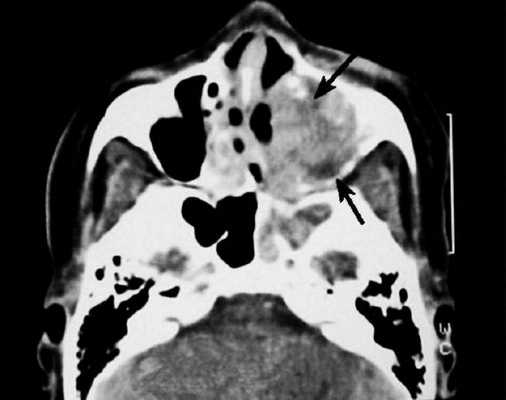

Чтобы узнать степень распространенности патологического процесса, обычно назначают компьютерную томографию носа и околоносовых пазух, иногда с контрастом. В некоторых случаях для дифференциальной диагностики проводят магнитно-резонансную томографию носа и придаточных пазух.

Фото - Рак носоглотки, с распространением на окологлоточное пространство (стрелкой указана зона инвазии)